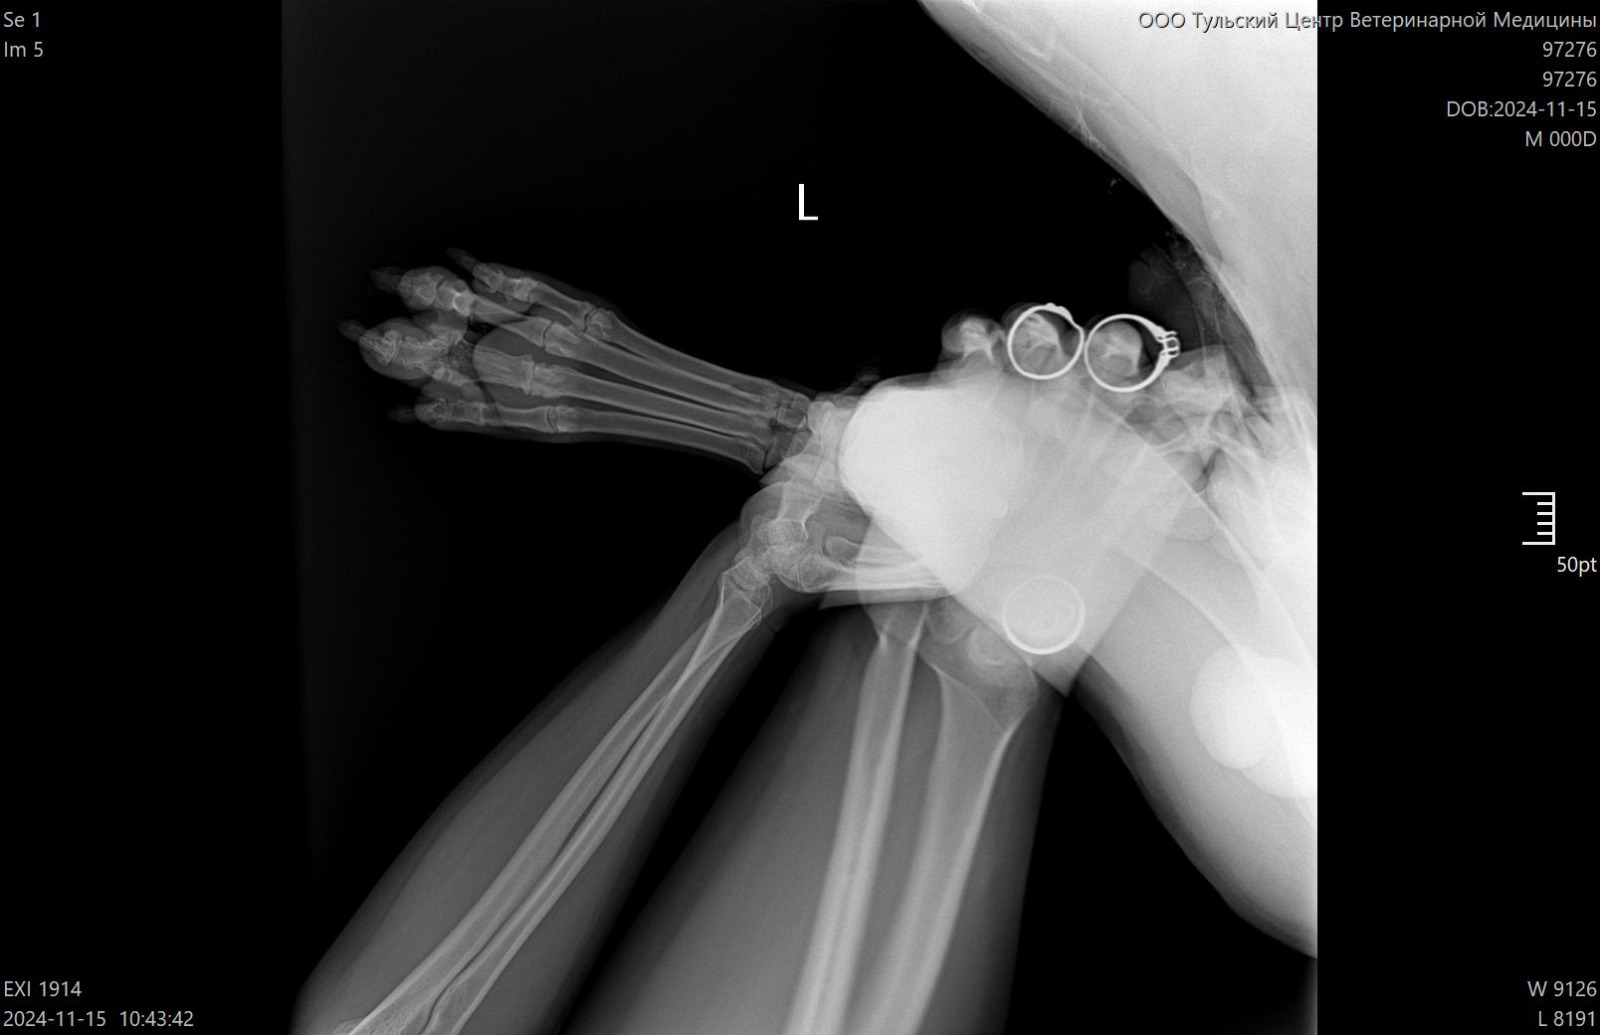

Рентген лапы, которая болит

Зона операции в снимок не попала....но со слов врача все нормально. То что видно - чисто....придется поверить, но так как шов подтекает, антиюиотик попробуем заменить на клиндомицин.

Сильнейший коксартроз тбс на больной лапе.....который не заметили на первичных осмотрах....зато настаивали в необходимости кастрации. В результате изменения положения лапы, нагрузки - воспаление и боль.